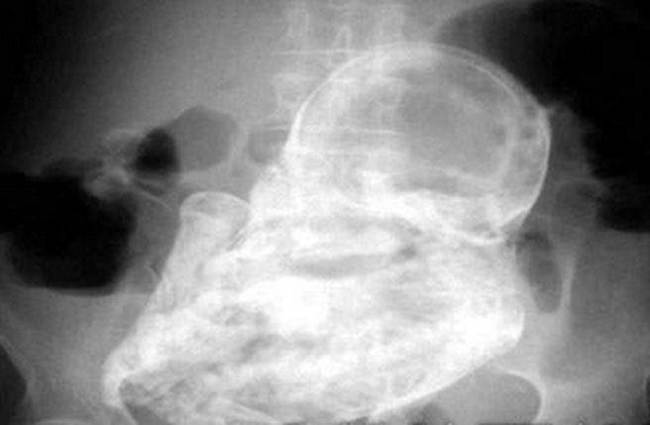

gif_animation インドにて、突然腹部の痛みを訴え出した4歳の少年を両親が病院へ連れて行き検査を受けさせると、少年は胎児を ”妊娠” していた…。50万分の1ほどの確率で起こる「寄生胎児」という症例。主には双子の兄弟として生まれてくるはずだった片方の胎児が、無事に生まれてきたもう片方の赤ちゃんに寄生するというもの。その後この寄生胎児は遺体となって摘出されたそう。[2]images

※ 画像は4歳の少年のレントゲン、2枚目は参考として

「11歳の少女の背中に残された寄生胎児」